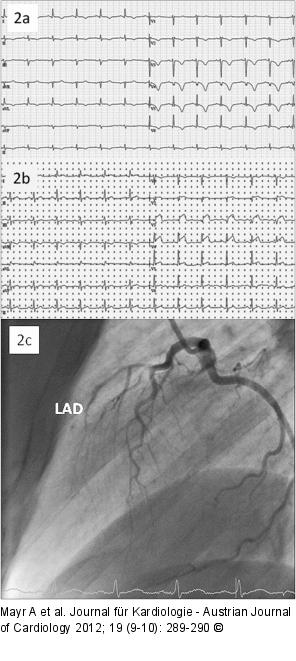

Abbildung 2a-c: STEMI a): ECG one day after the first coronary angiography showing subacute anterior STEMI; (b): ECG three days after the first coronary angiography showing again significant anterior ST segment elevations; the patient once again developed massive retrosternal chest pain; (c): Second coronary angiography revealed complete occlusion of the proximal LAD due to spontaneous dissection. |